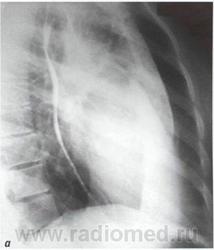

В правой передней косой проекции определяются ранние и самые выразительные признаки увеличения левого предсердия. При этом тень сердца проступает в ретрокардиальное пространство, частично или полностью занимая его, или даже накладываясь на тень позвоночника.

По мере увеличения левого предсердия пищевод, тесно прилегающий к его задней стенке, отклоняется кзади и вправо. Степень уменьшения ретрокардиаль - ного пространства, протяженность дуги и ее радиус воспроизводят форму левого предсердия и позволяют судить о степени его увеличения. При чистом или преобладающем митральном стенозе отклонение пищевода происходит по дуге малого радиуса.

Рентгенологические признаки дилатации левого предсердия в правой косой проекции с контрастированным пищеводом: а, б, в - I, II и III степени увеличения левого предсердия.

В норме ретрокардиальное пространство на уровне левого предсердия составляет не менее 3 см. При первой степени увеличения левого предсердия ретрокардиальное пространство сужено до половины. При второй степени контрастированный пищевод располагается уже в задней половине ретрокарди - ального пространства. При третьей степени тень сердца и контрастированный пищевод накладываются на тень позвоночника .

Заметно все большее отклонение контрастированного пищевода кзади и сужение ретрокардиального пространства.